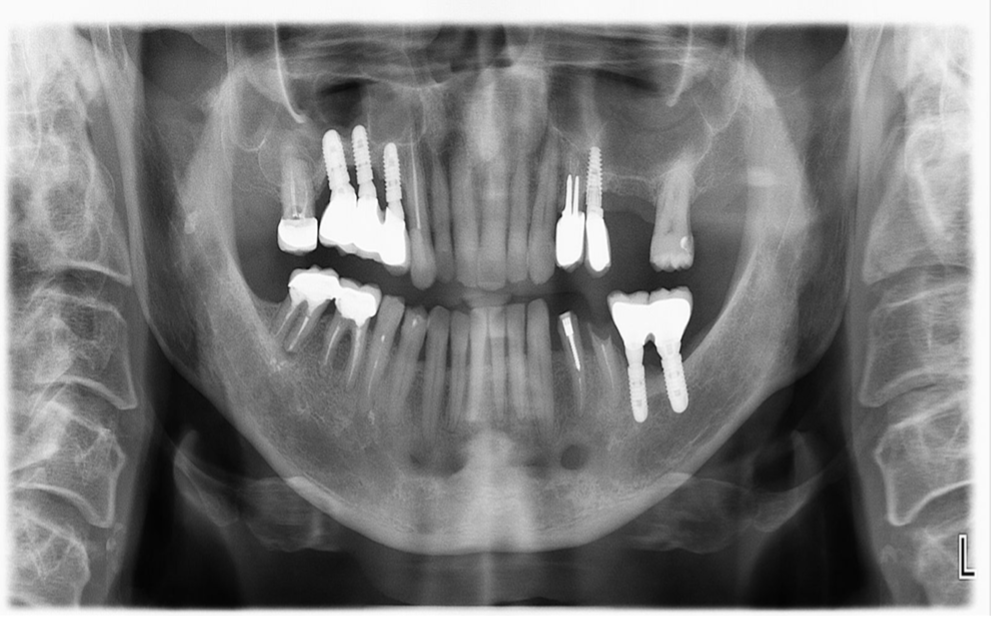

Рентгенологическое исследование позволяет выявить металлические включения в полости рта